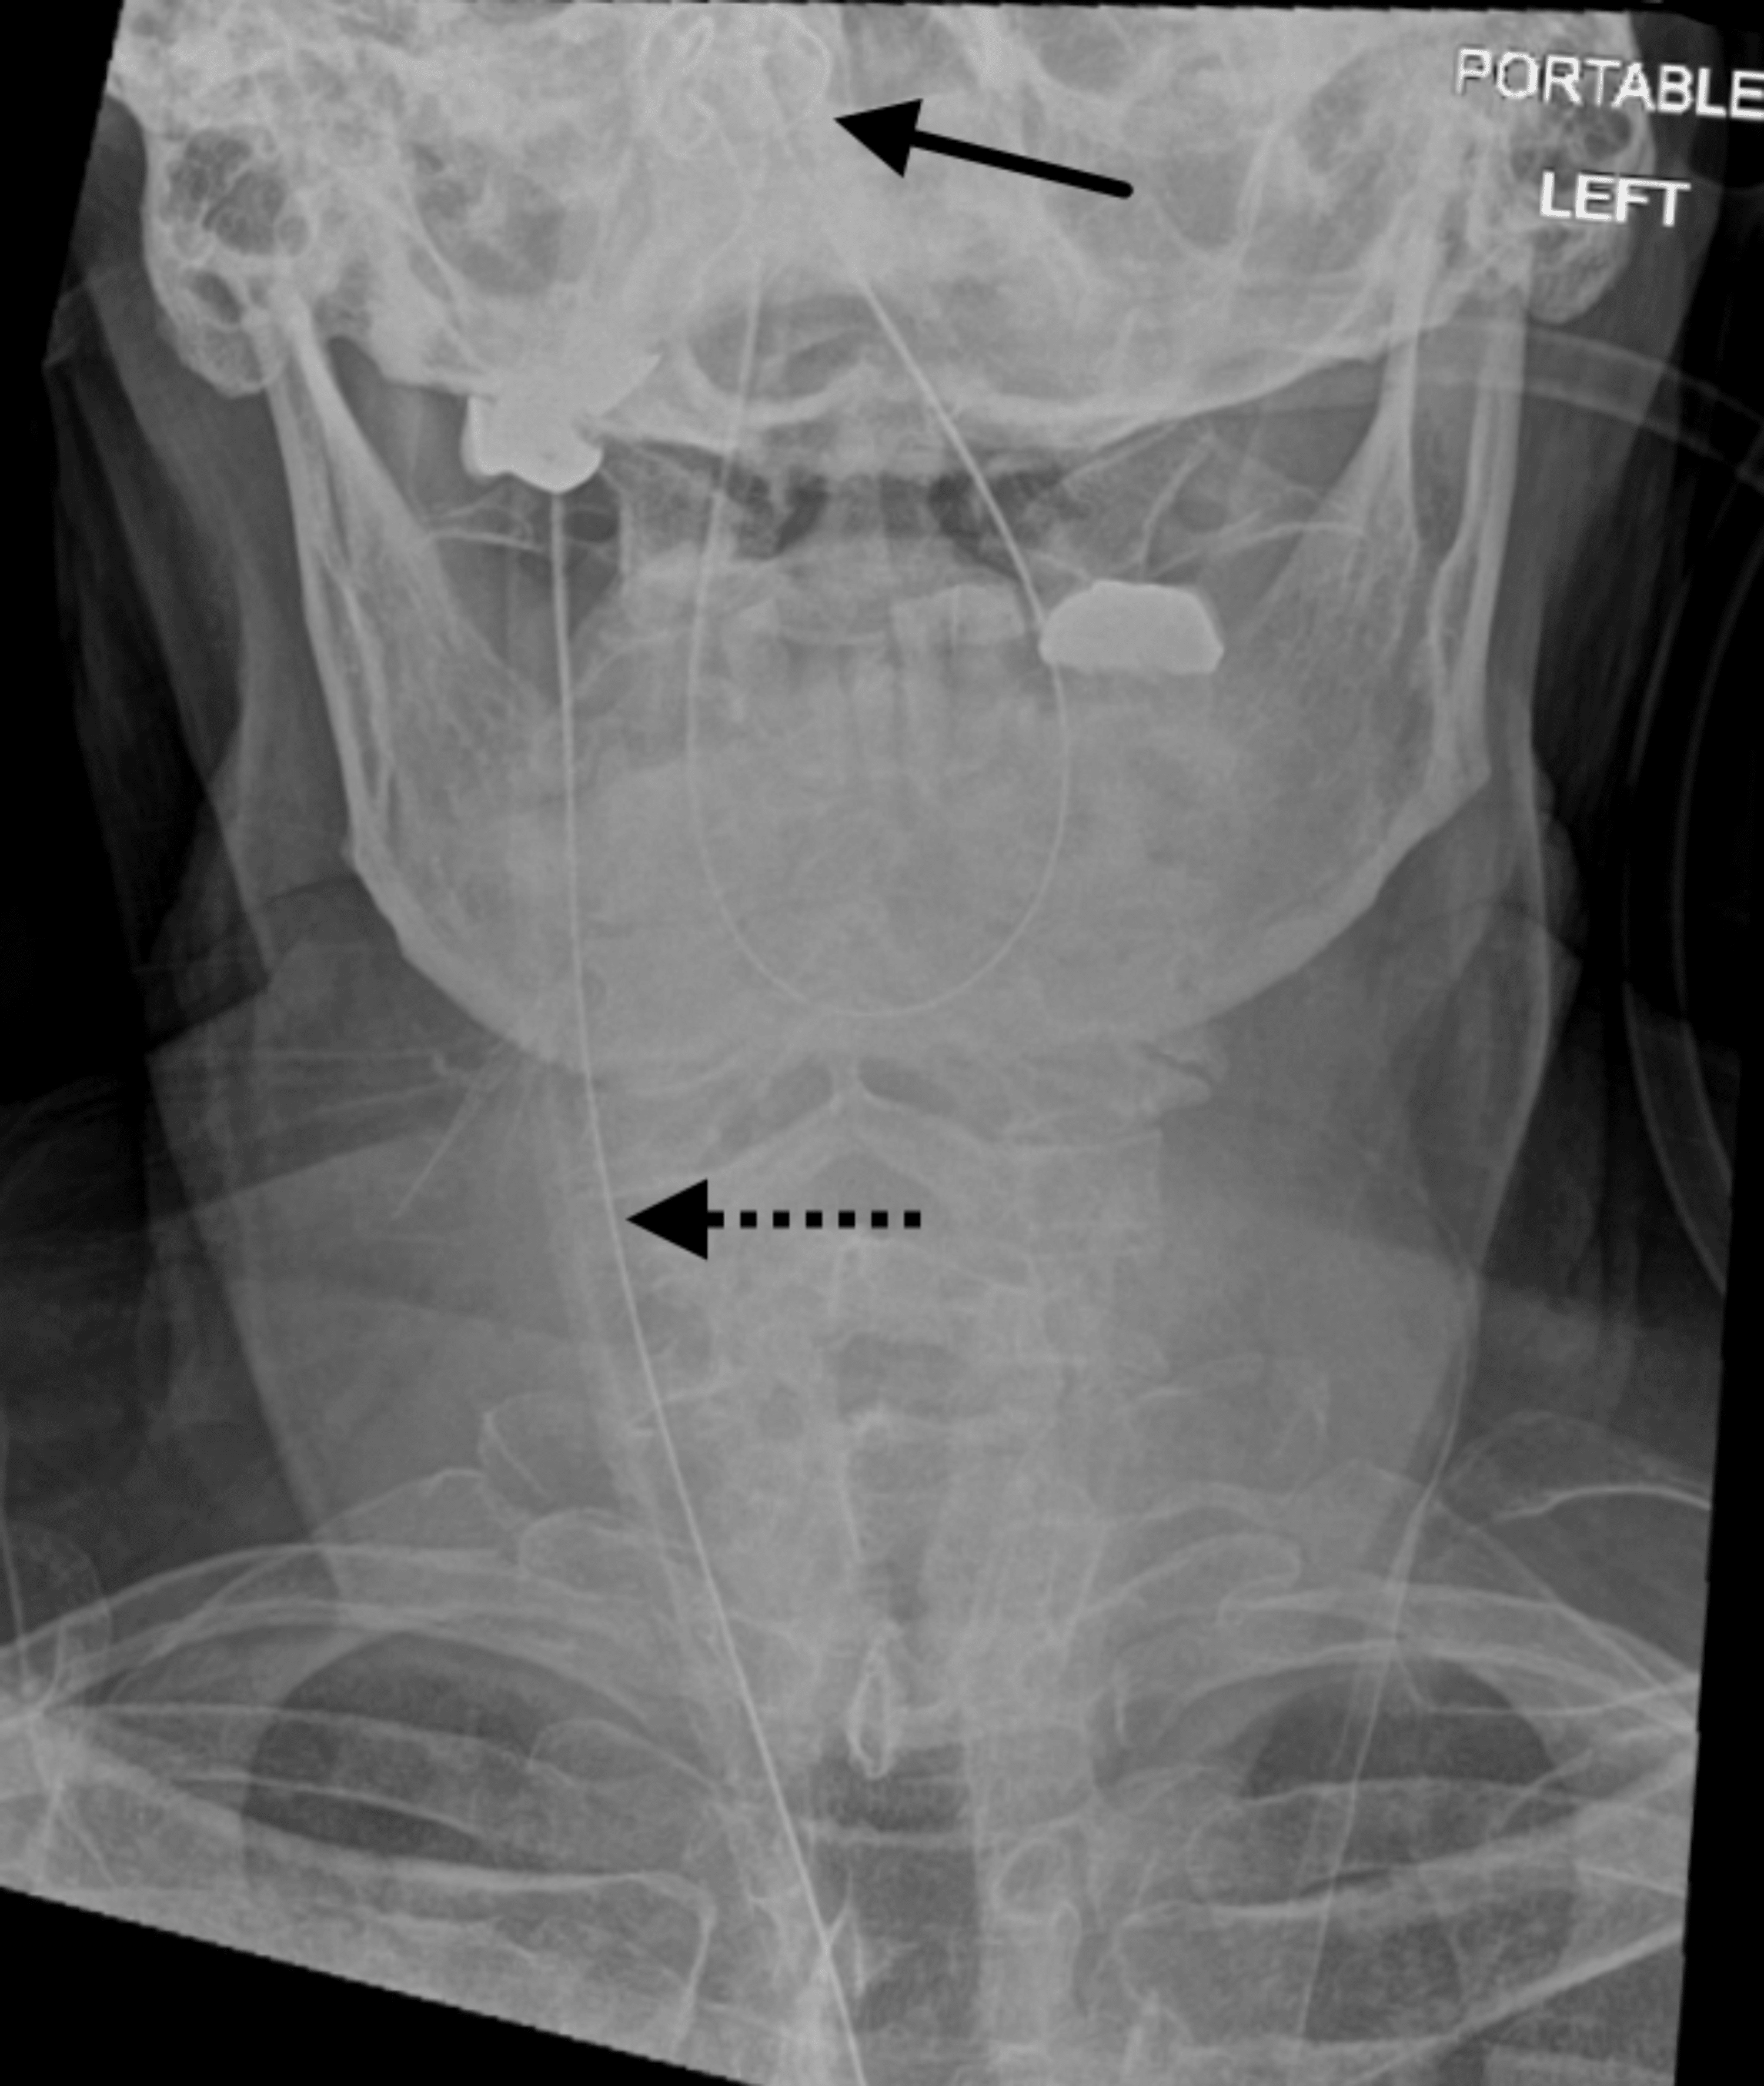

Pediatric Nasogastric Tube Malfunction / Malposition / Misposition

Nasogastric Tube X Ray Can Nasogastric Tube Cause Damage — nasogastric/nasoenteric tube related adverse events are relatively common and the majority involved. — enteric tubes that will be removed within a short period of time can also be passed through the mouth. A nasogastric tube (ng tube) is a thin, flexible plastic tube that’s used for temporary. — the ideal location for an ng tube placed. Can Nasogastric Tube Cause Damage.

Misplaced nasogastric tube Image Can Nasogastric Tube Cause Damage — nasogastric/nasoenteric tube related adverse events are relatively common and the majority involved. — the ideal location for an ng tube placed for suction is within the stomach because placement past the pylorus can cause damage to the. — an outline on risks involved with the use of nasogastric tubes, with advice on how to use them. Can Nasogastric Tube Cause Damage.